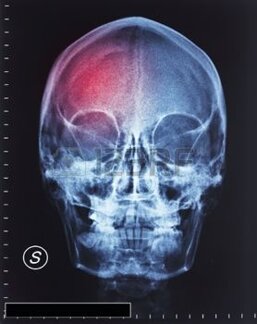

TRAUMA CRANICO

Presso il nostro studio il trattamento è centrato sulle conseguenze fisiche, motorie, cognitive, comportamentali ed emotive del trauma cranico. La fase riabilitativa comincia dopo la dimissione dalla struttura ospedaliera. Abbiamo formato un'equipe specializzata ed integrata che pone al centro la persona e la sua famiglia, che svolge un ruolo attivo nella riabilitazione: il Neurologo, medico che valuta e prescrive il trattamento riabilitativo al vostro familiare seguendolo durante tutto il percorso riabilitativo e nel follow-up e integrando le diverse competenze del team. Neuropsicologo: attraverso un accurato esame neuropsicologico, valuterà periodicamente il profilo cognitivo del vostro familiare. Mediante l'uso di test psicodiagnostici standardizzati, individuerà i deficit cognitivi presenti nelle diverse aree della memoria, del linguaggio, l'orientamento, l'attenzione, la capacità di ragionamento, la percezione, ecc., le abilità residue, le modificazioni della personalità e le eventuali problematiche caratteriali. Compito del neuropsicologo sarà anche quello di verificare a distanza di tempo dal trauma, la remissione o progressione dei deficit segnalati, nonché indagare l'insorgere di eventuali disturbi psicologici che possono aggravare il quadro cognitivo e fisico del paziente. Lo Psicologo Psicoterapeuta, competente per quanto riguarda i problemi psicologici e le turbe comportamentali osservabili nei pazienti con trauma cranico, è previsto un sostegno psicologico o se necessario una psicoterapia breve. Il Fisioterapista che si concentra sul recupero neuromotorio. Quindi sviluppa programmi individuali di trattamento per il recupero delle diverse abilità motorie e sensitive di concerto con tutte le altre figure del nostro team. Il terapista mostrerà anche ai familiari le azioni più adeguate per integrare il trattamento neuromotorio. Il Logopedista che facilita tutti gli aspetti della comunicazione, inclusa la produzione di suoni, l'espressione verbale, la comprensione, la lettura, la scrittura.